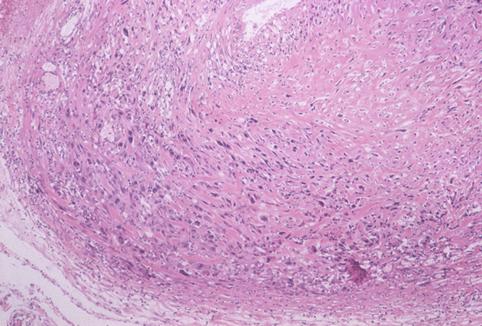

部位(按器官分)食道/中

检查方法病理切片(微观)

肿瘤的肉眼分类0型(表在型)/IIc型(IIc)

肿瘤最大直径40以上

肿瘤的深度sm